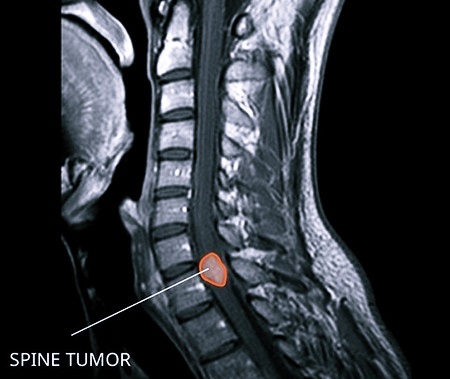

Первое место в плане обнаружения опухоли спинного мозга принадлежит МРТ позвоночника. Томография позволяет уточнить место расположения новообразования, оценить объем и степень распространения. По ее результатам врач может сделать предварительные выводы о строении опухоли.